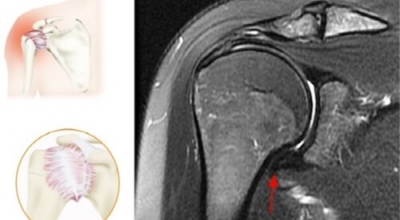

오십견이란 어깨의 통증과 어깨관절의 운동범위 제한을 특징으로 하는 질환으로 특히 50대 이후에 많이 발생함으로 오십견이라 이름이 지어졌으며 어깨관절이 얼어붙었다는 뜻으로 동결견(frozen shoulder)이라고도 합니다. 어깨관절의 운동성이 소실되기 때문에 옷 입기, 머리 감기, 물건 들기 등의 일상생활에 많은 어려움이 유발되며 통증에 의하여 잠을 못자는 경우도 대개 발생하게 됩니다.

오십견 치료방법은 도수치료, 프롤로주사, 핌스(FIMS) 등 비수술적 방법을 적용합니다. 이 중 도수치료는 마취통증의학과 전문의의 정밀한 진단을 바탕으로 해부학적 지식이 많은 치료사가 진행하는 수기 치료입니다. 치료사가 손과 소도구를 사용해 손상된 관절을 바로잡고, 경직되고 틀어진 주변 근육과 연부조직을 이완해 통증을 보완해 줍니다. 수기로 진행하는 만큼 환자의 증상과 상태에 따라 강도를 유연하게 조절하는 맞춤 치료가 가능합니다.

프롤로주사는 근골격계 초음파 영상 유도하 주사치료 중 한 개로 고농도 포도당 용액을 주입해 염증을 제거하고 손상된 조직을 재생하는 치료이며 근본적인 까닭을 개선할 수 있어 근골격계 통증에 많이 적용되어요. 이는 마취나 절개 등의 방법이 필요 없고 인체에 무해한 성분을 사용하므로 고령자나 만성질환자들도 받을 수 있습니다.

핌스치료는 프롤로테라피(Prolotherapy)와 핌스(Functional Intramuscular Stimulation)가 결합한 치료입니다. 약물을 이용하여 관절에 발생한 염증이나 유착을 제거해 준 다음 특수 바늘로 굳은 근육을 이완하는 비수술적 방법입니다. 고령자나 고혈압과 같은 기저 질환이 있는 환자에게도 적용할 수 있습니다.